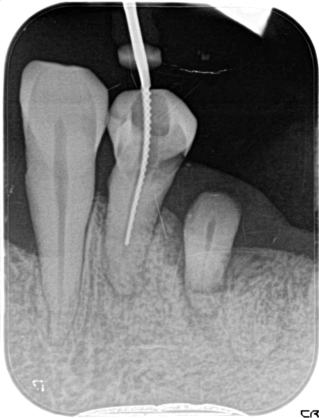

歯内療法:根管の湾曲:神経はまっすぐとは限らない